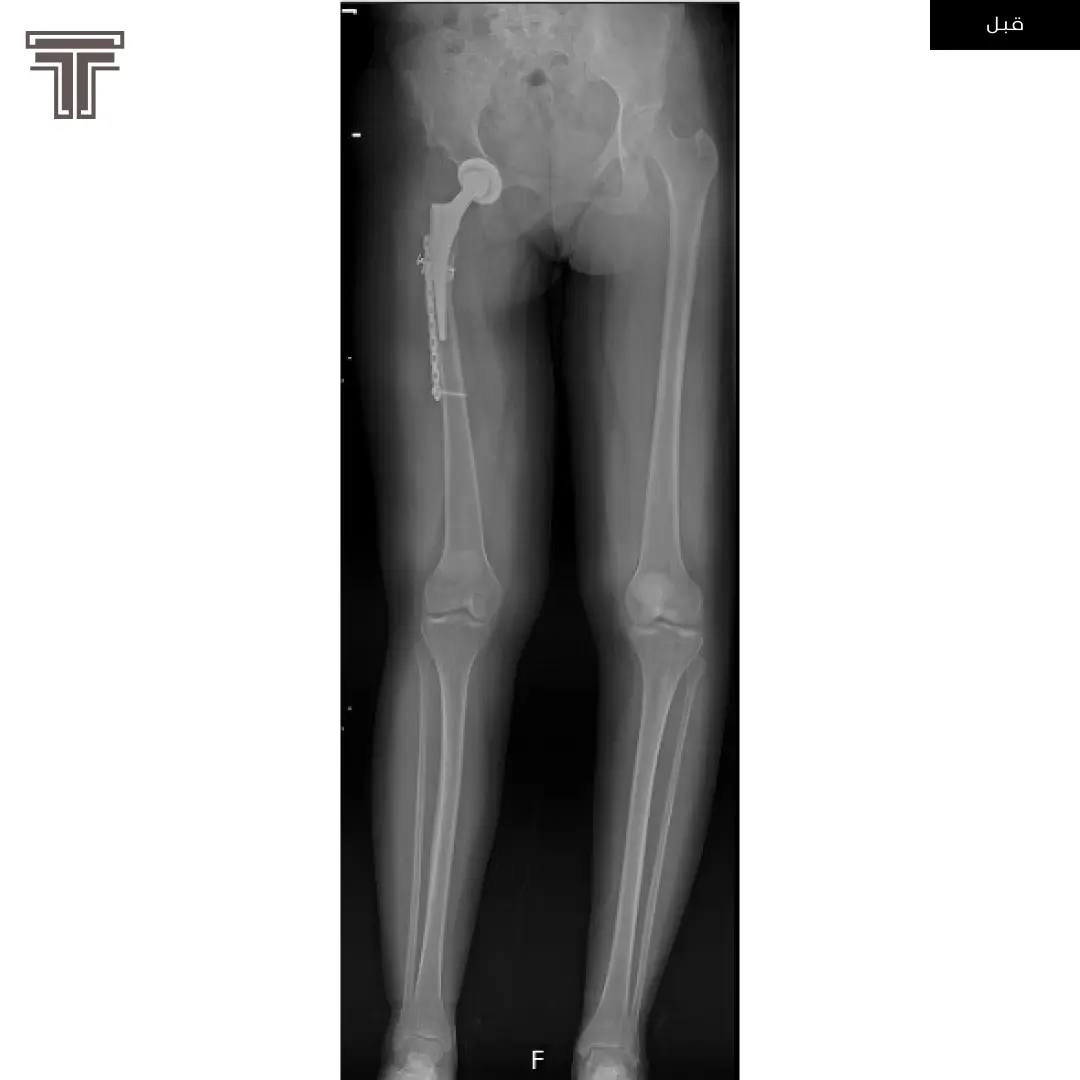

عندما تهمل خلوع الورك الولادية لعمر كبير يصبح علاجها وارجاعها صعب ويتطلب عملية استبدال للمفصل. وفي مثل هذه العمليات وتحديدا في استبدال مفاصل خلوع الورك الولادية يتطلب تقصير في طول الفخذ لتجنب المضاعفات.